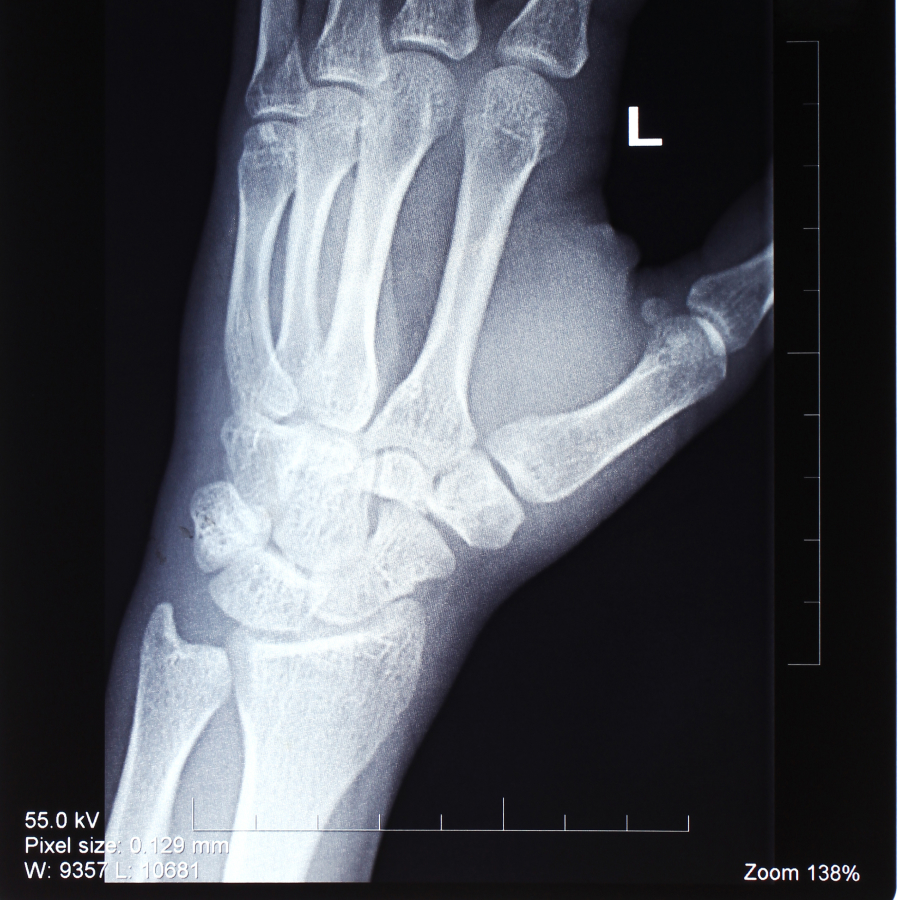

Muñeca